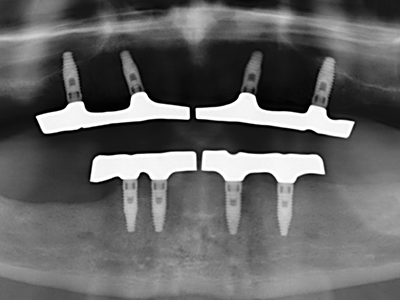

As shown in the past, basically any bone surgery procedure represents a possible indication for piezo surgery. Thus preparation of the mobile segment in distraction osteogenesis (Fig. 23-25) and sandwich osteotomy uses special attachments without endangering the blood supply to the crestal section, which is essential for the success of both techniques (Gonzalez-Garcia, Diniz-Freitas et al. 2008).

For removal of an implant, a vestibular bone cover that is replaced after removal of the implant screw can be prepared to retain the contour of the alveolar ridge.

There are additional applications in sinus surgery. Pathologies and foreign bodies can be removed from the sinus after concentric preparation of a generally trapezoid bone cover in the facial sinus wall. The bone cover is repositioned on conclusion of the intra-antral operation component and secured by wedging or adaptive sutures to prevent dislocation.